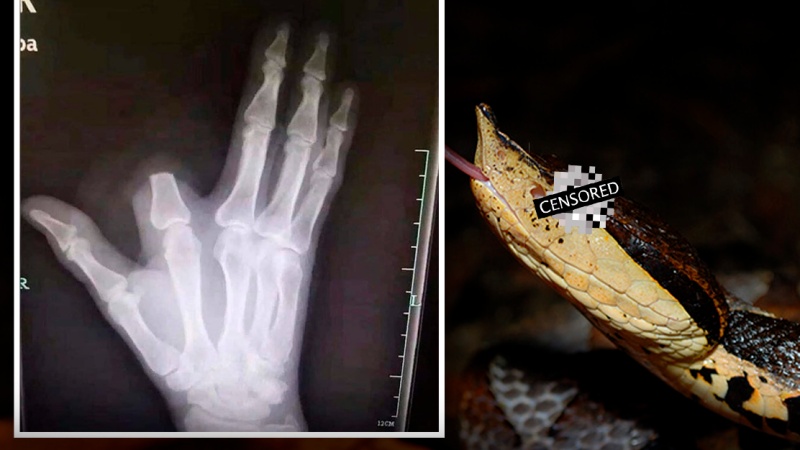

วันหนึ่งนาย Zhang ชายวัย 60 ปี ขึ้นไปตัดไม้บนเขาในเขตชางหยู มณฑลเจ้อเจียง และโดนงูกัดเข้าที่นิ้ว

งูตัวนั้นคือ “งูห้าก้าว” ตามตำนานของจีนแล้ว เป็นงูพิษร้ายแรง หากโดนกัดเข้าให้แล้ว เดินไม่ถึงห้าก้าวได้อิเซไคแน่นอน เป็นที่มาของชื่อมันนั่นเอง

งูห้าก้าวเป็นงูสปีชีส์ Deinagkistrodon ที่เป็นเครือญาติกับงูหางกระดิ่ง มีพิษร้ายแรงจริง และถ้าไม่ได้รับการรักษาอย่างทันท่วงที ก็อาจจะทำให้ถึงแก่ชีวิตได้ เพราะพิษของมันจะส่งผลต่อการเกาะตัวของลิ่มเลือด

ด้วยความตกใจแกก็เลยตัดสินใจตัดนิ้วทิ้ง เพื่อรักษาชีวิตของตัวเองเอาไว้ ตามตำราหรือคำบอกเล่าที่ได้รับฟังมาแต่โบราณ